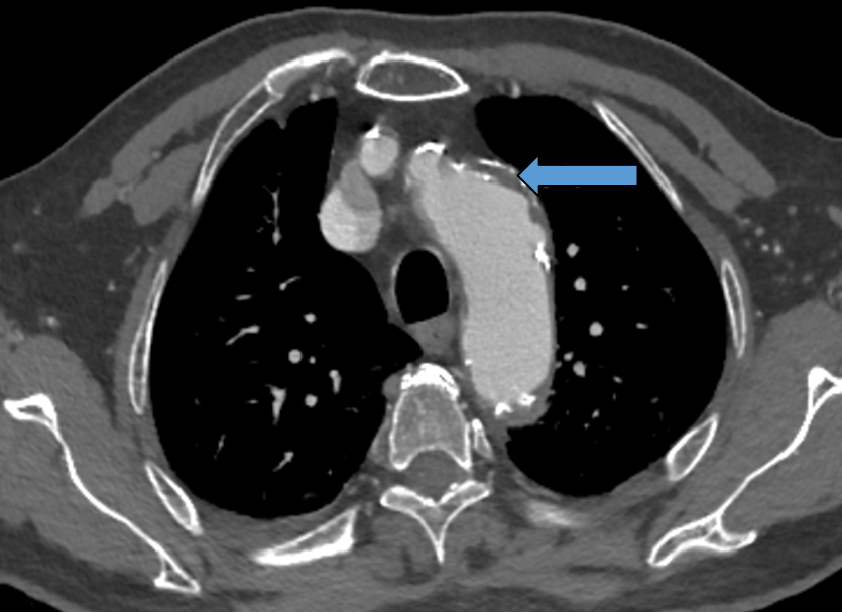

病例:包膜下血肿

术后第二天:腹胀,血常规:血色素10.4g,肾功能指标稍高

术后第三天:血压下降85/50mmHg,心率增快,胸闷加重。血常规示血色素7g,肾功能异常。CT右肾包膜血肿,后腹膜血肿